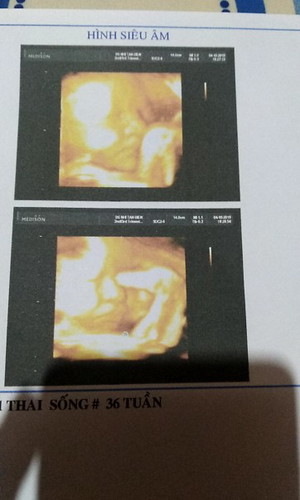

e cua me 37w